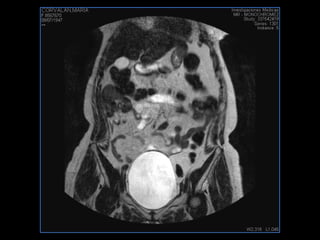

PROTOCOLO abdomen COR T2, AXIAL supresion grasa AX T1 +SAG T2  CON   GADOLINIO :  COR T1+AX T1(DIN) SAT: NO  FASE: RL THK: 6MM  COIL:  GAP: (FACTOR 1.4) 2MM FOV: 40 CM NEX:2 SINCRONIZACION RESPIRATORIA EN 3 O 4 CICLOS ALE

resonancia de abdomen